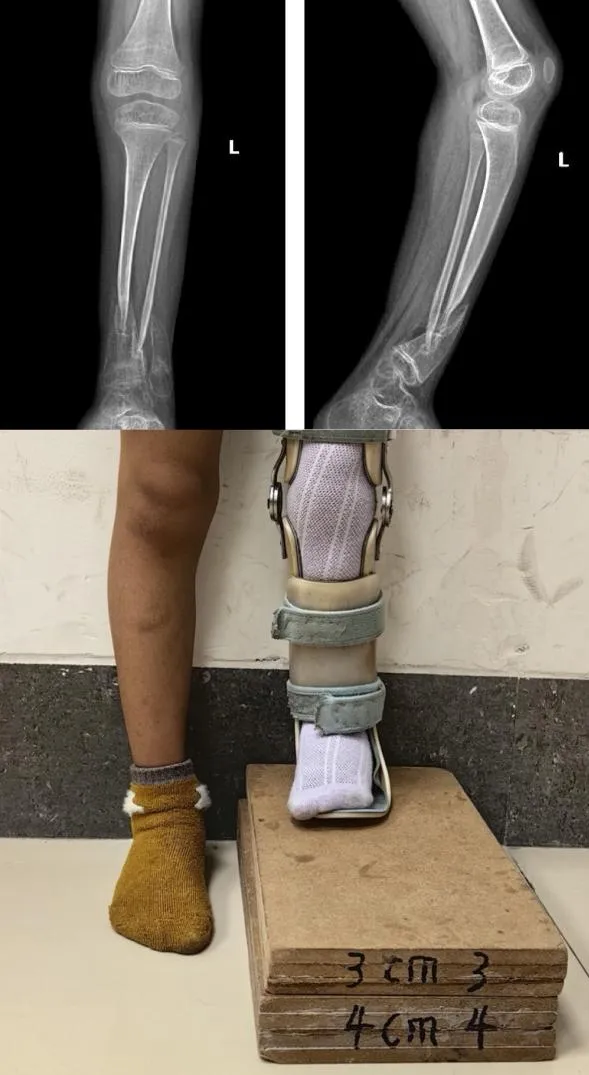

小雨父母多方辗转,带着她来到了郑州市骨科医院。接诊后,郑州市骨科医院小儿骨科的专家为小雨制定了手术方案:“假关节病灶切除+髓内棒固定+自体髂骨移植+环形外固定架加压”“切除病灶、取自体髂骨移植、植入髓内棒、安装外固定架……” 经过数小时的手术,“手术很成功”。

经过几个月的康复训练,复查显示:小雨的胫骨假关节已经实现骨性愈合,下肢力线完美,可以和正常小朋友一样,奔跑、玩耍了!